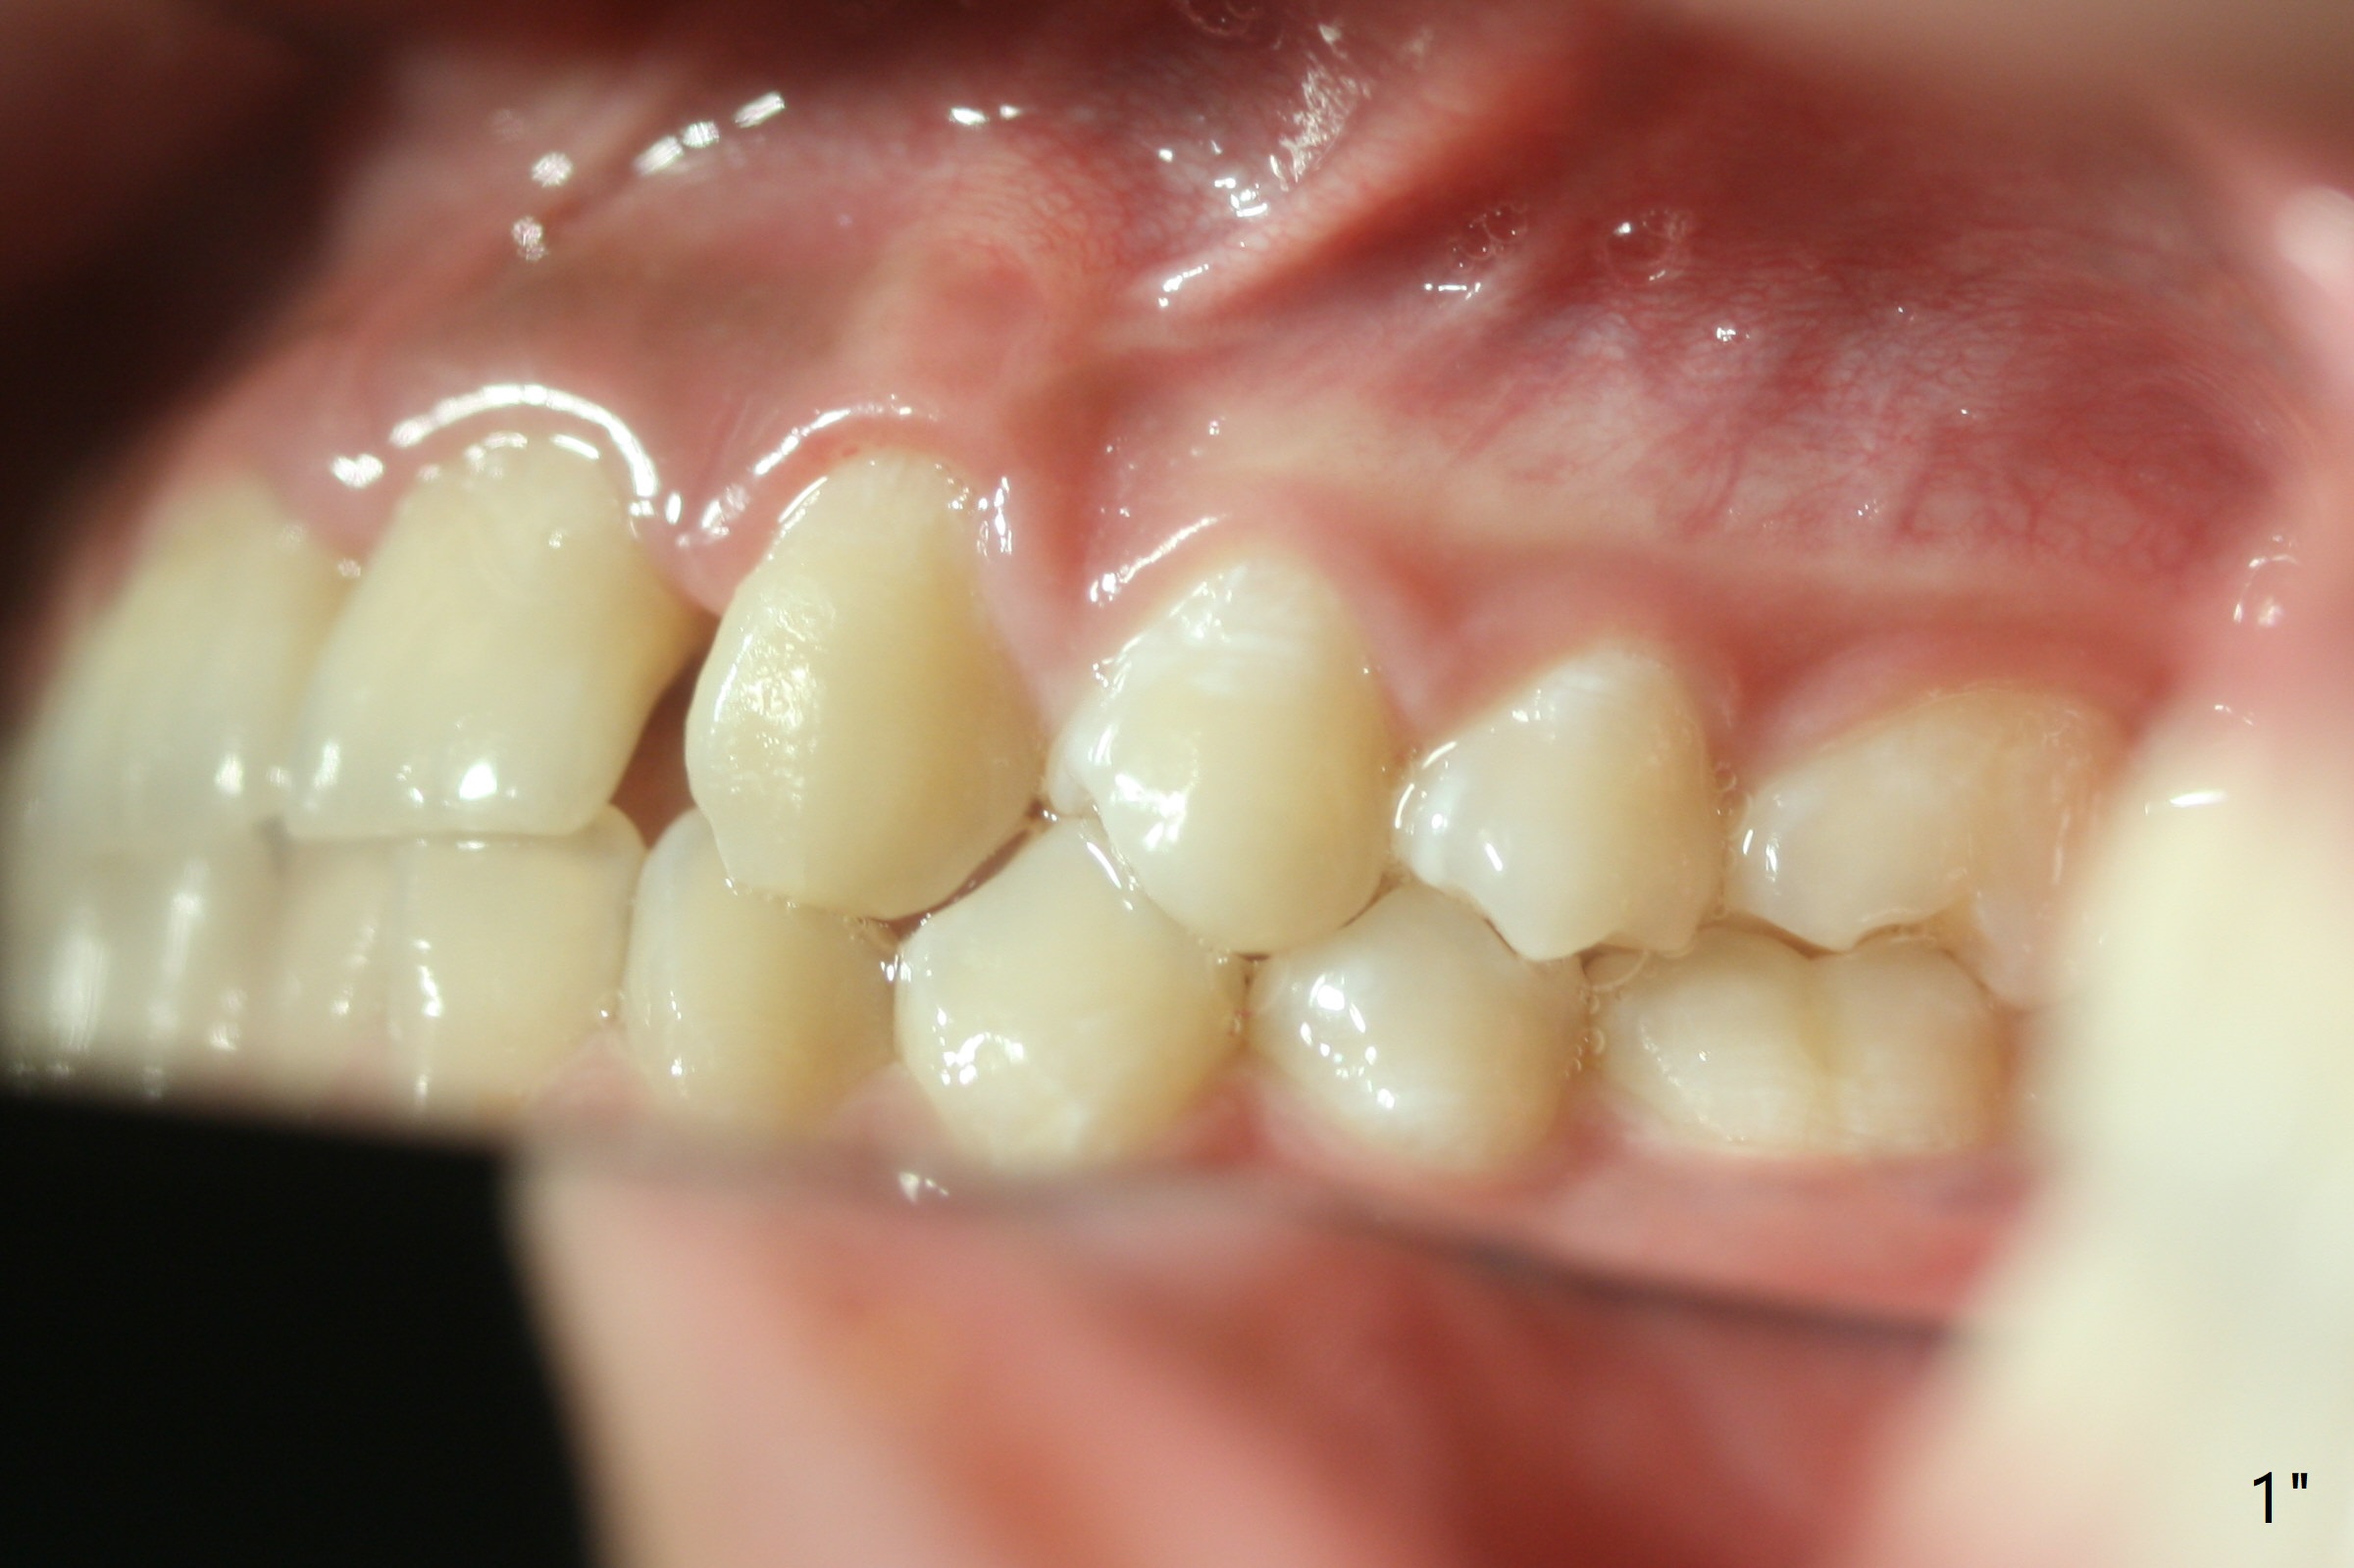

Bracketing for Congenital Missing Lateral